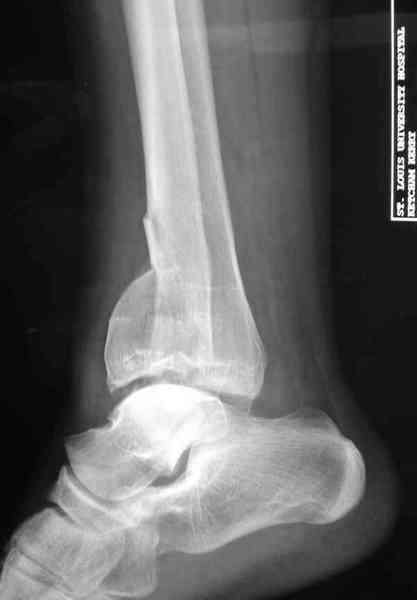

Открыто или закрыто - это уже зависит от опыта и

наличия материала. Минимальным аппаратом Илизарова или одним из Contoured Medial или Antero-Lateral Locking Plate из лимитирванного доступа не имеет значения, но самое главное необходимо добиться репозиции сустава.

Аутокость является самым надежным материалом, но при желании можно применить синтетический заполнитель Osteoset Pallets - структуральный материал, по аннотации материал через определенное время интегрируется в кость.

Здесь выставлена пара случаев перелома пилона, оба

случая леченные этапным наружным фиксатором.

Второй случай фиксирован аппаратом Илизарова.

Djoldas Kuldjanov, MD

Department of Orthopedic Surgery

St. Louis University Medical Center